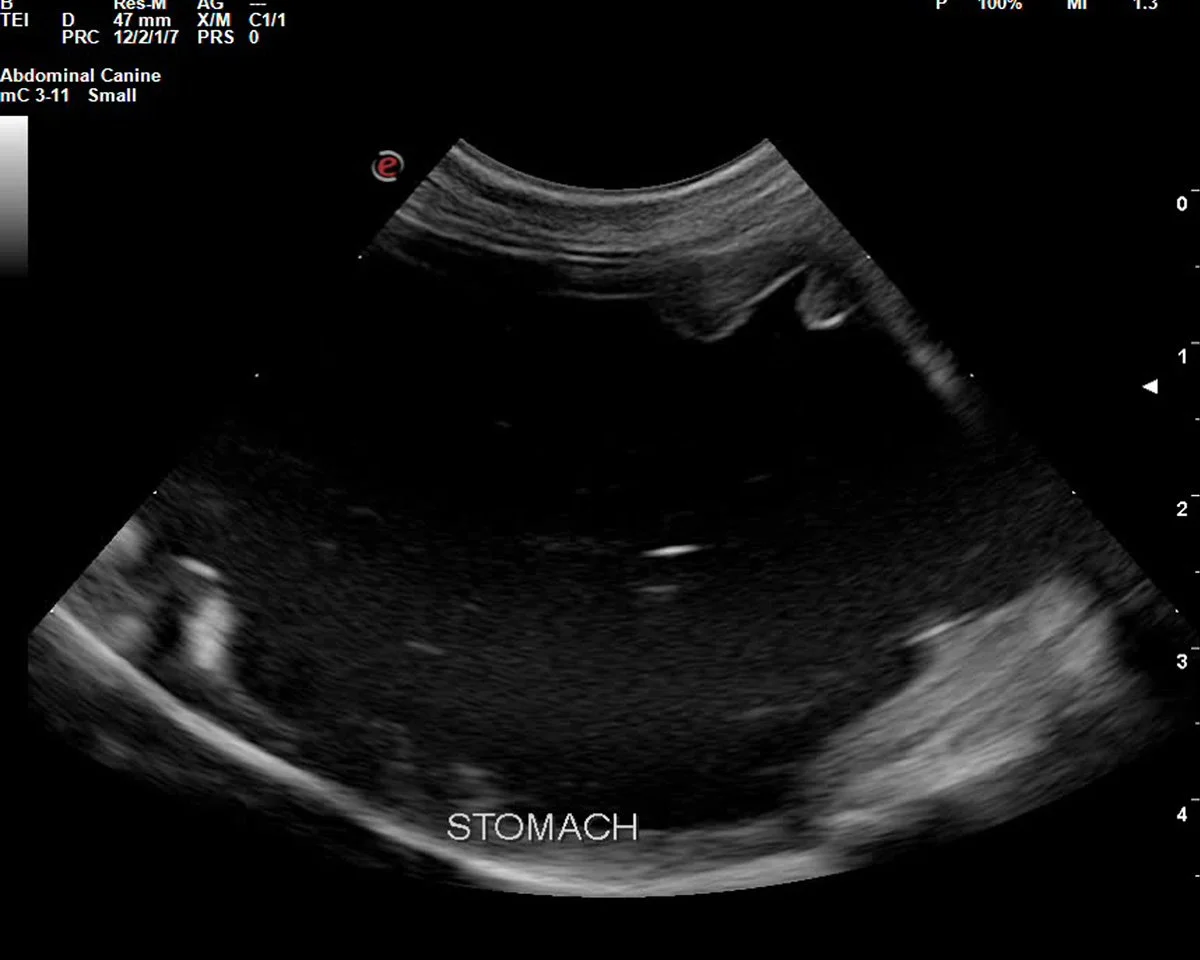

Echipa Patrupet a inițiat un panel de urgență, pentru stabilirea rapidă a unui diagnostic a cauzei stării critice. Analizele de sânge au evidențiat dezechilibre electrolitice și markeri sugestivi pentru hipoadrenocorticism, care au dus la suspiciunea principală: boala Addison. Mai mult, ecografia abdominală a evidenţiat un stomac destins de conținut lichid, motilitate gastrointestinală redusă și inflamație la nivel intestinal.